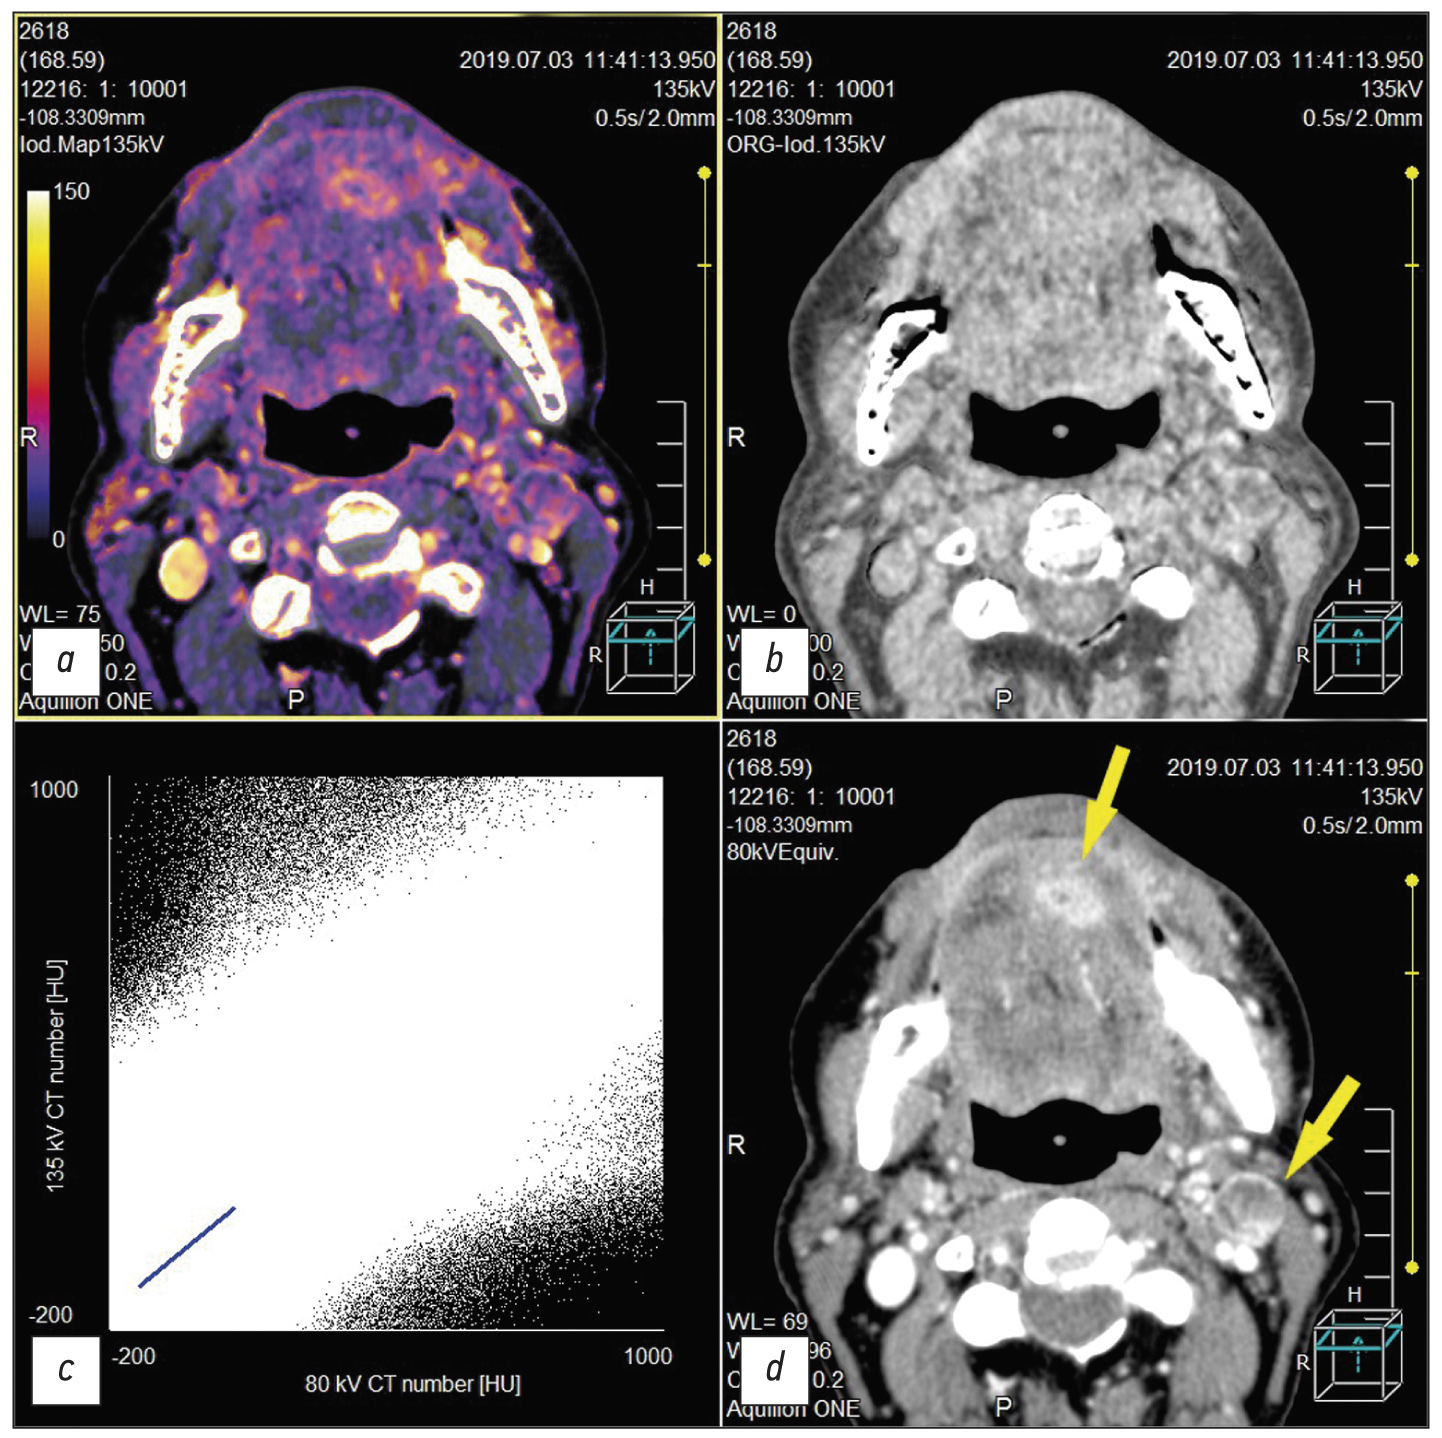

The fundamental principle of dual-energy computed tomography (DECT) is based on the fact that different anatomical structures and tissues may have the same or different density depending on the X-ray energy under which they are exposed, that is, in the range between high and low kW values. The primary advantage of using dual-energy systems is the ability to decompose the images into underlying materials. In this case, different attenuations at various X-ray energies are recorded. This reveals how much of each material is present in a particular voxel of the image and expands the possibilities for postprocessing the obtained image volumes (Figure). For example, the construction of virtual non-contrast images, subtraction of bone structures, and analysis of radiopaque stones are possible. In addition, iodine maps with isolated iodine images may be generated.

Fig. Dual-energy computed tomography after chemo radiotherapy for squamous cell cancer of the mouth floor that had spread to the tongue. Residual tumor on the lower surface of the tongue and metastasis with decay to the submandibular lymph node on the left (yellow arrows). a, iodine map; b, virtual non-contrast image; с, pixel distribution plot for an individual slice between high and low kV values; d, monochromatic image with a low value equal to 80 kV